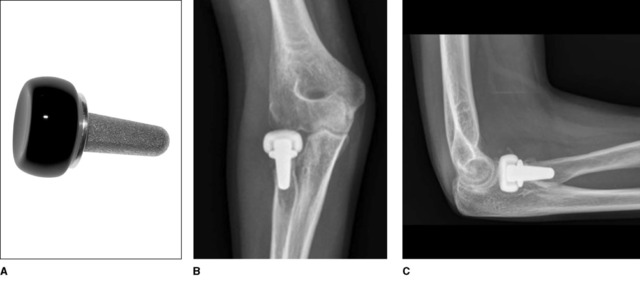

压配型柄假体(press-fit stems)

压配型假体的假体柄通常进行喷砂处理或者进行等离子喷涂来保证假体柄可以和桡骨颈髓腔紧密贴服(图 6)。该类型假体也为组装式设计。假体头具有和原始桡骨头一样的桡骨头凹和偏心距。喷砂处理的钛合金假体柄具有粗糙的外表面,和等离子喷涂的假体柄相比,喷砂处理的假体柄被认为可以提供更好的原始压配稳定性,但是这两种方式处理的假体柄都还存在一定程度上可以接受的微动。等离子喷涂的假体柄被认为可以取得获得更好的骨质长入,对于长柄型假体更为有利。压配型假体的假体柄与桡骨髓腔相匹配。由于假体柄与髓腔贴合在一起,假体不能在髓腔内活动,因此必须在正确的位置放置假体。手术过程中,当过度扩髓放置过大的假体柄时会发生桡骨干骨折。

图 6 压配型解剖型桡骨头假体系统的轴位(左)和侧位(右)相。该假体具有组合式的钛合金桡骨头以及喷砂的钛合金假体柄。桡骨头具有和人体自身桡骨头相一致的凹和偏心距。

Moro 等人使用压配型桡骨头假体治疗 25 例(24 个患者)Mason-Johnston 分型 III 型和 IV 型桡骨头骨折。取得了良好疗效,健康测量量表 SF-36 明显改善,17 例肘关节的 Mayo 肘关节表现评分为优,患者的主观满意度评分平均为 9.2(满分 10 分)。肘关节的屈曲弧度平均为 28 至 140。17 例肘关节存在假体柄的放射透亮影,但是在平均 39 个月的随访期间没有一例患者因为疼痛或假体松动而需要去除假体。随后进行的一项使用压配型钴铬桡骨头关节治疗的 16 例患者的研究报道结果与其相似,该项研究的患者骨折类型包括新鲜、陈旧性桡骨头骨折以及肘关节骨折脱位,作者发现了一个有趣的现象,新鲜骨折患者的 DASH 评分以及肘关节运动要优于陈旧性骨折,虽然该优势并无显著统计学意义。

最近又有一项 37 例压配型桡骨头关节置换的文献报道,平均影像学随访 50 个月,作者发现有 9 例患者因为假体松动而去除假体,除此之外还有另外 3 例患者出现了假体松动但保留假体。作者认为假体松动一般发生在术后早期(平均为术后 11 个月),通常需要去除关节假体。他们的临床结果中患者肘关节的活动度与之前文献报道的结果相似,但是作者并未评估报道去除假体组患者的临床结果。

由此来看,压配型假体的短期临床效果较佳,但是和松配型假体相比存在较高的假体松动率和假体去除率。导致上述情况的原因可能主要是由于压配型假体柄不能活动以及不能适应肱骨小头的解剖形态。术中因素假体未被放置于解剖位置也有可能造成后期假体松动和疼痛,从而需要去除假体。如果桡骨头关节不能完成顺滑的肘关节运动,从长期来看,由于受到应力载荷的影响必将出现假体松动。此时可能需要去除假体,但这会造成后期桡骨向近端移位。根据目前的证据,压配型桡骨头关节置换确实可以重建肘关节稳定缓解疼痛和改善运动,但是出现假体松动导致翻修的可能性较高。